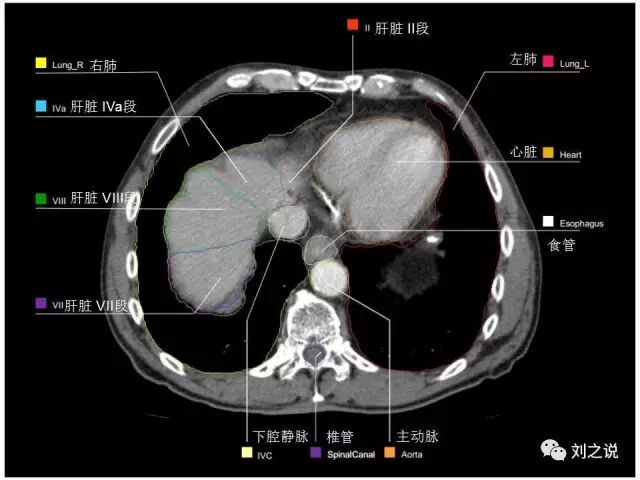

参考RTOG共识和3D-body解剖。

来源:刘之说